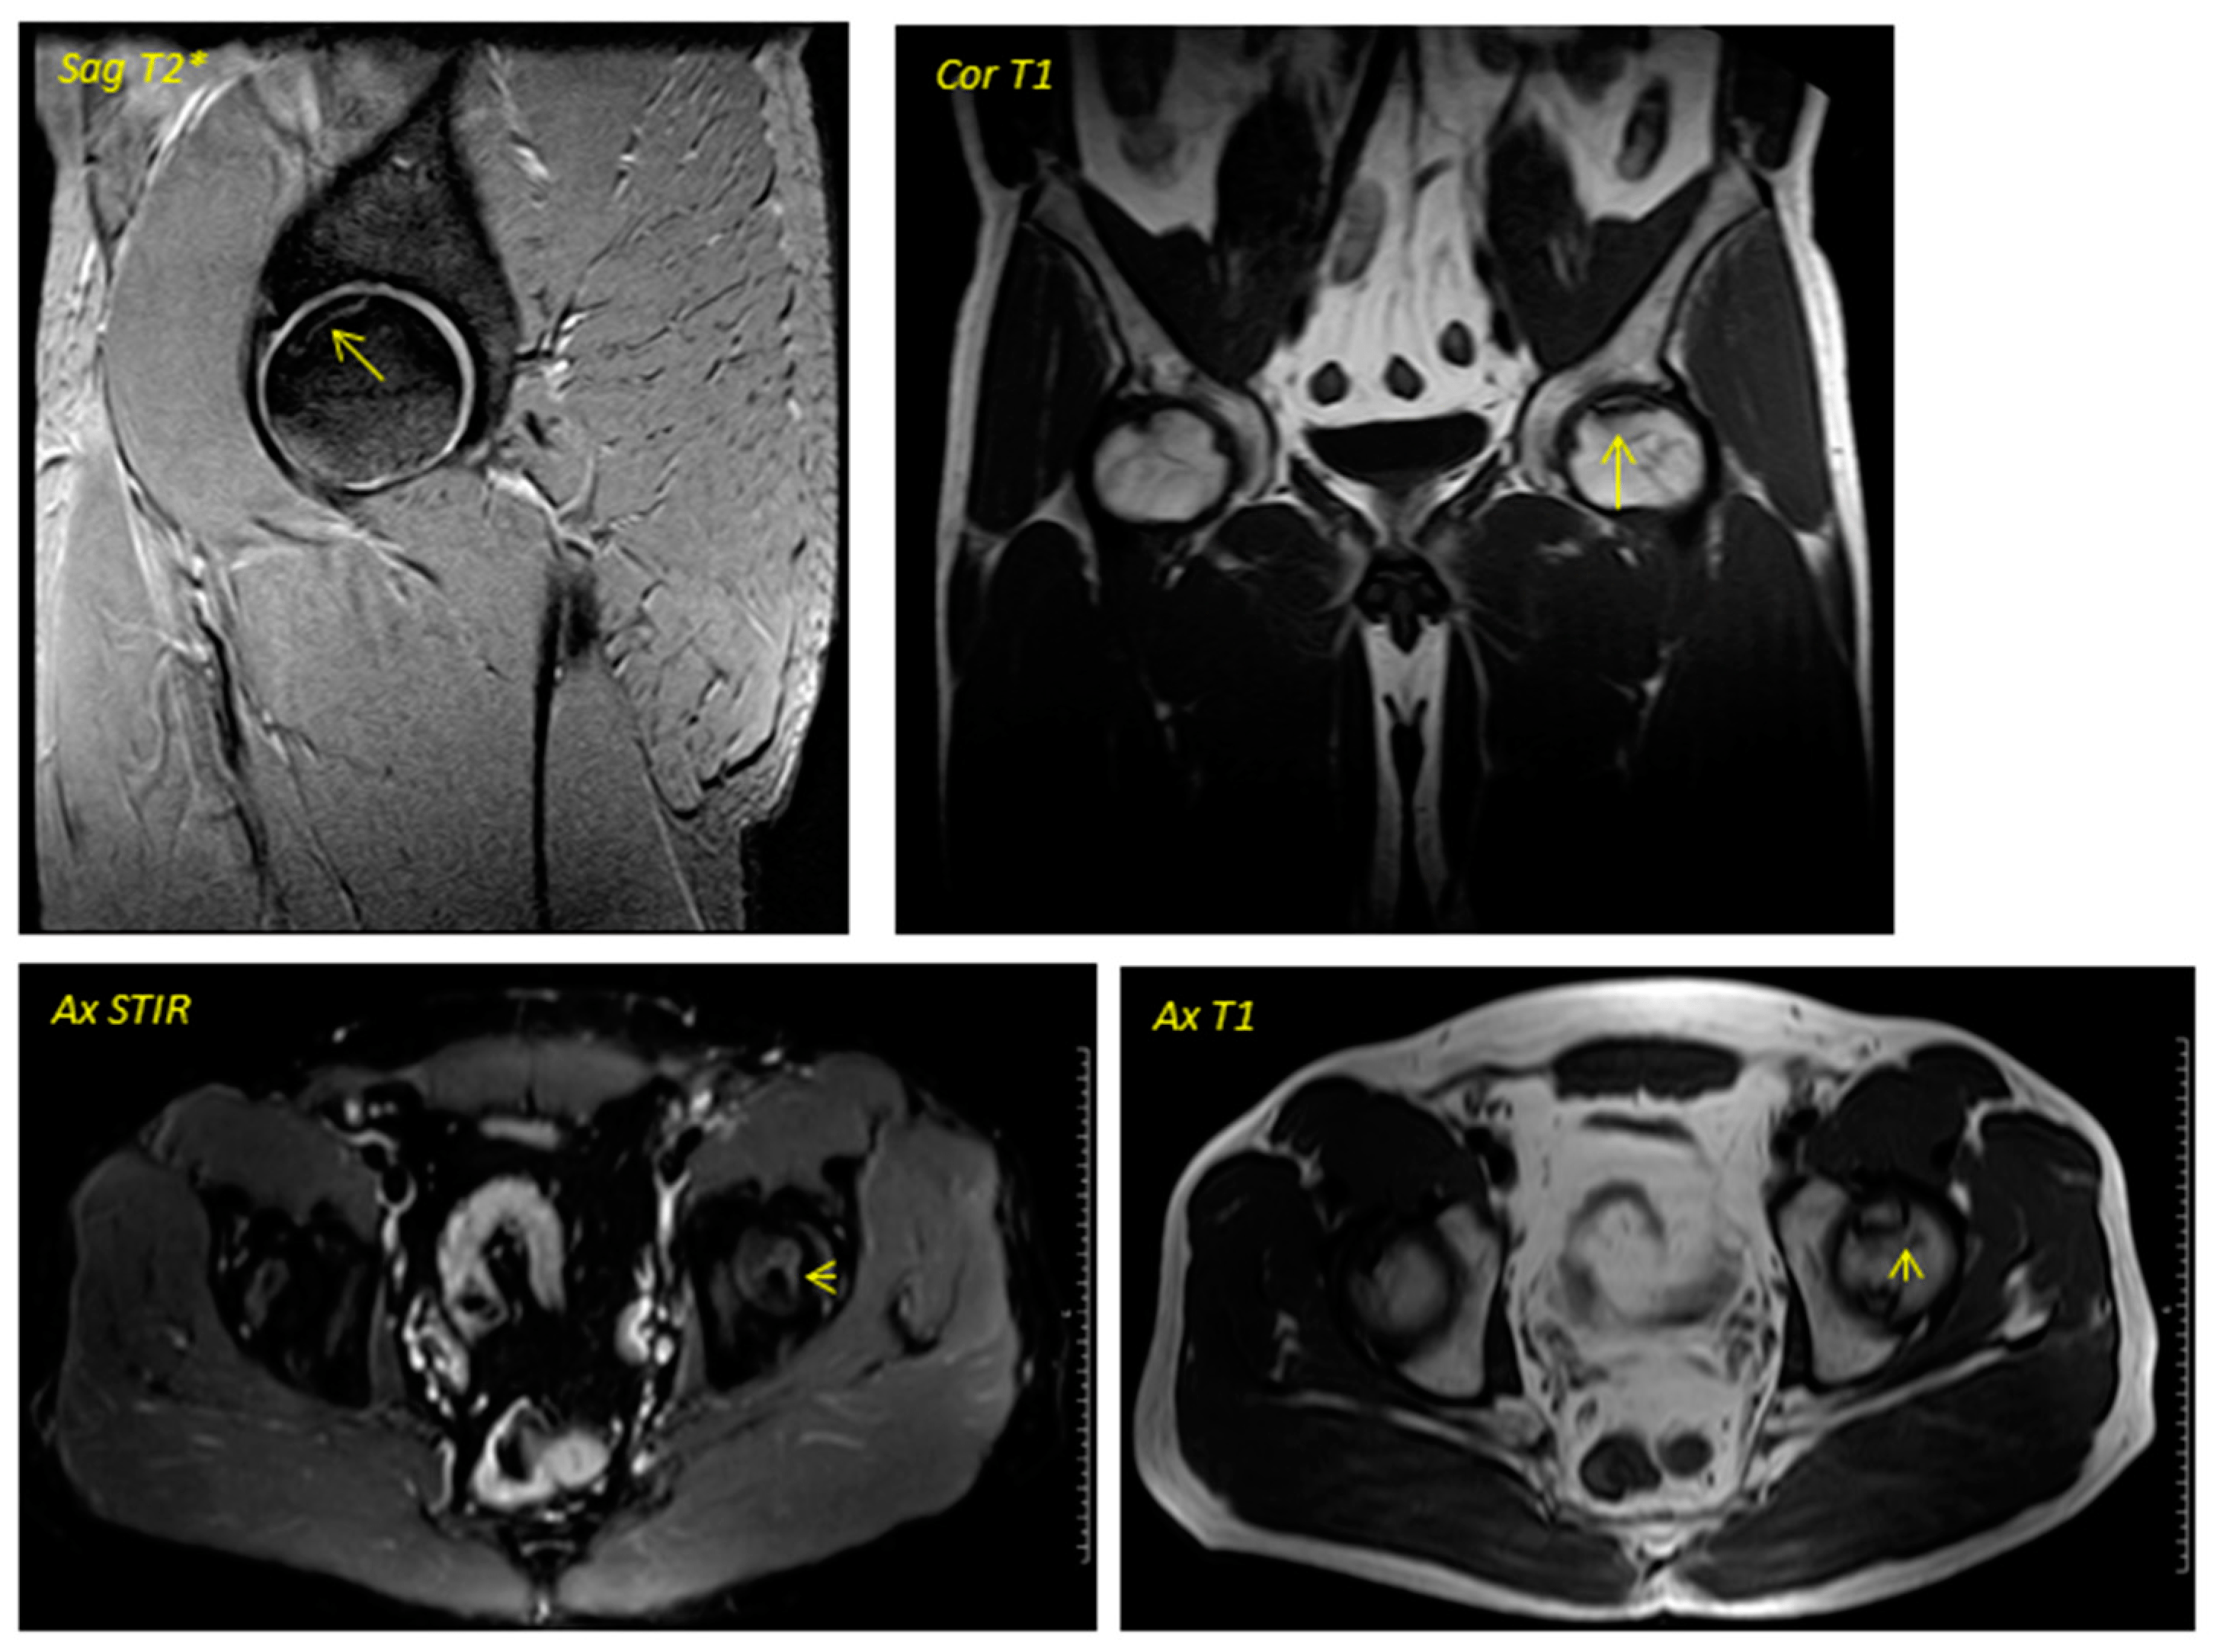

關于影像學研究,在12個月的隨訪期間,在影像學演變中觀察到了一些發現(圖1和圖2)。

首先,方向的變化從第六個月開始出現在所有病例中,而在早期階段并不明顯。其次,62.5%的患者 ( n=5) 在手術后的第一年內實現了影像穩定。第三,兩名患者 (25%) 出現壞死區進展,而一名 (12.5%) 患者出現明顯的再骨化跡象。盡管觀察到描述性差異,但后一個參數的p值在統計學上并不顯著。

圖1:對應于2013年12月執行的一名38歲男性的術前圖像

圖2:對應于圖1中患者的術后磁共振成像于2016年4月進行